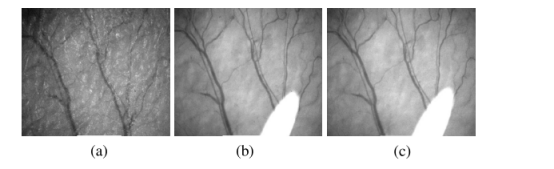

就像所有的光学成像技术一样,激光散斑血流成像技术也受限于成像深度,对皮肤表面的血管和血流能够成像,再深层就很难进行观察。引入活体光透明系列技术,不但可以提升激光散斑血流成像深度,而且提升了分辨率,以下的实验结果表明活体光透明后激光散斑血流成像的结果更清晰,背景更为“清澈”。

图a为小鼠耳朵激光散斑图像,图b为透明化5min后图像,图c为10min后图像